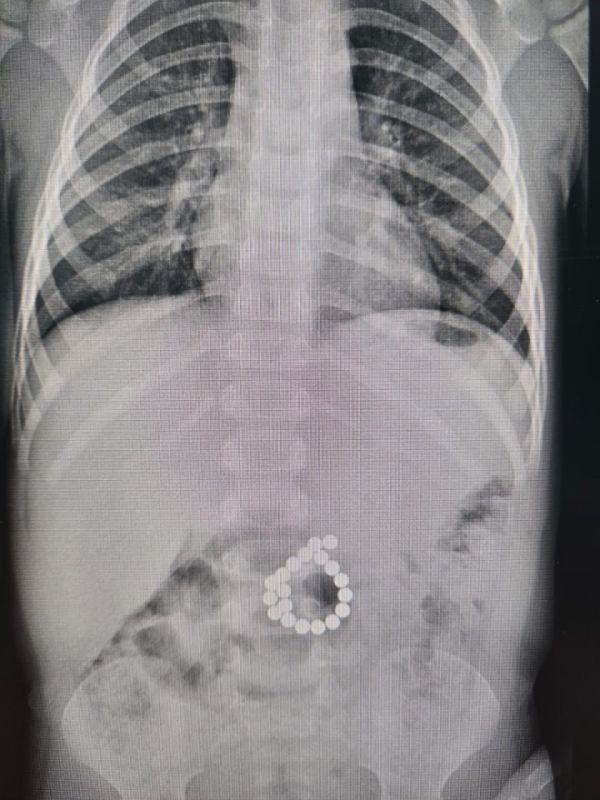

Девочка, которой два с половиной года, находилась на лечении в ожоговом центре. У ребенка поражено до 40% поверхности кожи.

Для оказания высокотехнологической медицинской помощи было принято решение о переводе пациента в больницу Нижнего Новгорода.